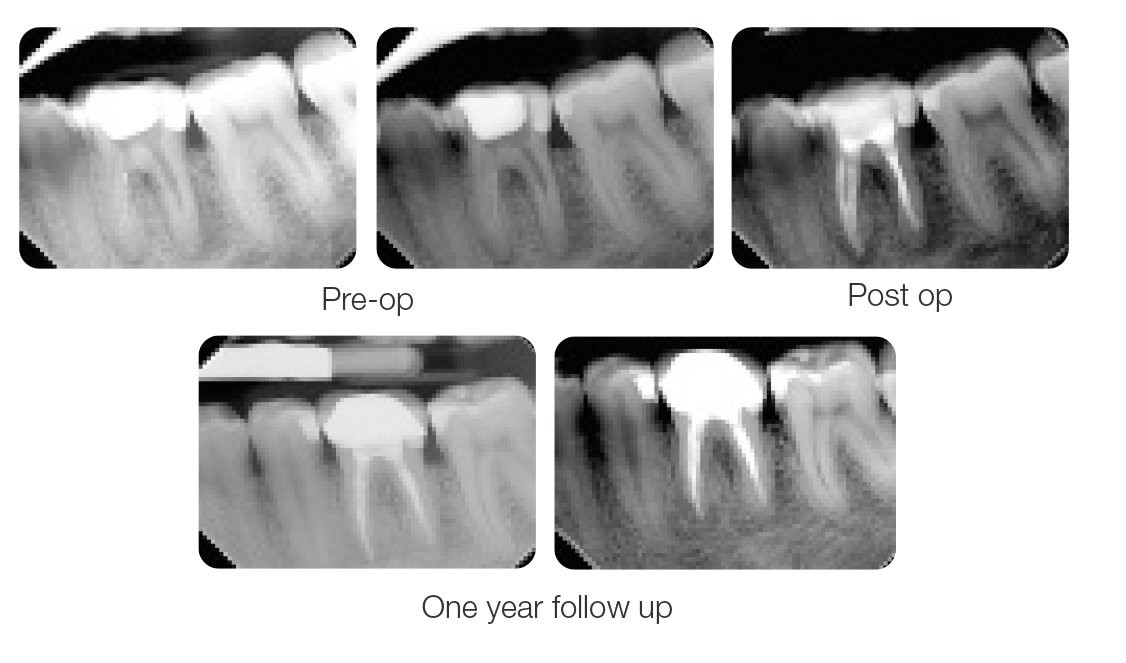

Case 1: 46 years old Male patient, ASA 1, presented for the evaluation and the treatment of tooth #36. On clinical examination the tooth was sensitive to percussion and palpation. The radiographic examination showed a very large radiolucency on both mesial and distal roots, a separated instrument in the mesio-lingual canal. The diagnosis of previously initiated with symptomatic apical periodontitis was made, and the endodontic treatment was indicated.

Following aesthesia and rubber dam placement, access was performed, and canals were located. The coreonal fragment was removed and the apical fragment was bypassed. The canals were instrumented using Edge endo X7 files (EdgeEndo) to size 35.04 in the mesial canals and 40.04 in the distal canal.

Canals were obturated using hydraulic condensation using EdgeBioCeramic Sealer (EdgeEndo). Bioceramic cement was used for its antibacterial and bioactive properties. The one year follow up shows a complete healing of the lesion.